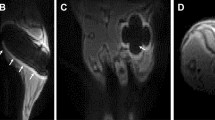

Impedance data distinguishes healing and poorly healing tibia fractures in an external fixator model. Histology sections in this image are stained with Hall’s and Brunt’s Quadruple (HBQ) stain and false-colored to aid interpretation of tissue composition. Blue = cartilage, yellow = trabecular bone, and purple = fibrous/amorphous tissue. Original red color = cortical bone, black/white area = bone marrow. (A) Representative histology section for an externally-fixed 0.5 mm defect at 14 days post-fracture; the fracture gap is clearly bridged by cartilage and new trabecular bone. (B) Representative histology section for an externally-fixed 2 mm critical-sized defect at 14 days post-fracture; the fracture gap is dominated by fibrous tissue. (C) Electrical resistance (R) at 15 kHz measured with a 250 µm sensor is plotted over days post-fracture for measurements taken in mice with 0.5 mm (N = 6) and 2 mm (N = 5) defects. Linear regression analyses determined that there is a significant positive relationship in mice with 0.5 mm defects (p < 0.0001), while there is no correlative relationship in mice with 2 mm defects. (D) Representative histology section for a healing mouse at 28 days post-fracture; the fracture gap is clearly bridged by cartilage and new trabecular bone. (E) Representative histology section for a poor-healing mouse at 28 days post-fracture; the fracture gap contains an overabundance of fibrous tissue. (F) Black arrow points to 56 µm sensor fully embedded in fracture tissue. (G) Electrical resistance (R) and reactance (X) normalized as a ratio to day 4 plotted over the course of fracture healing at 15 kHz. Normalized R and X both rise steadily over healing time in the healing mice, with stagnant values observed in the poor-healing mice. (H) Normalized R and X as a ratio to day 4 plotted over a range of frequencies at day 7 post-fracture. (I) Normalized R and X as a ratio to day 4 plotted over a range of frequencies at day 28 post-fracture. Marked shifts in frequency response from day 7 were observed in the healing mice, with limited change occurring in the poor-healing mice.

Impedance data distinguished femur fractures completely healed from those with varied healing in a bone plate model. Histology sections are stained and false-colored like in Fig. 2. (A) Representative histology section of a well-healed mouse at day 26; a large bony callus completely bridges the fracture ends. Black box outlines position of the high-magnification image in (B). (B) High-magnification image of (A) with black arrow pointing to the electrode fully-integrated in new trabecular bone. (C) X-ray radiograph of sample in (A). (D) Surface rendered, three-dimensional µCT image of sample in (A). (E) Representative histology section of a mouse with mixed healing at day 26; the fracture callus includes cartilage, fibrous tissue, and trabecular bone. Black box outlines position of the high-magnification image in (F). (F) High-magnification image of (E) with black arrow pointing to the electrode fully-embedded in the callus, surrounded by a mixture of new trabecular bone and fibrous tissue. (G) X-ray radiograph of sample in (E). (H) Surface rendered, three-dimensional µCT image of sample in (E). (I) R (normalized as a ratio to day 2) at 15 kHz plotted over days post-fracture. Data markers and lines are colored according to degree of healing – shades of red for mice sacrificed at day 12 (F1, F2, F3), shades of blue for mice sacrificed at day 26 that healed well (F4, F5, F6), shades of purple for mice sacrificed at day 26 that healed poorly (F7, F8), and shades of brown for control mice sacrificed at day 26 (C1, C2). Normalized R clearly rises at a faster rate in two mice with complete bony calli, F4 and F5. (J) X (normalized as a ratio to day 2) at 100 kHz plotted over days post-fracture. Normalized X clearly rises at a faster rate in two mice with complete bony calli, F4 and F5. (K) Impedance data at all measured frequencies is fit to an equivalent circuit model (inset), and the R2t parameter is extracted, normalized as a ratio to day 2, and plotted over days post-fracture. This analysis is able to clearly distinguish the samples that are classified as union by orthopaedic surgeons (F4, F5, and F6 in Table 1).